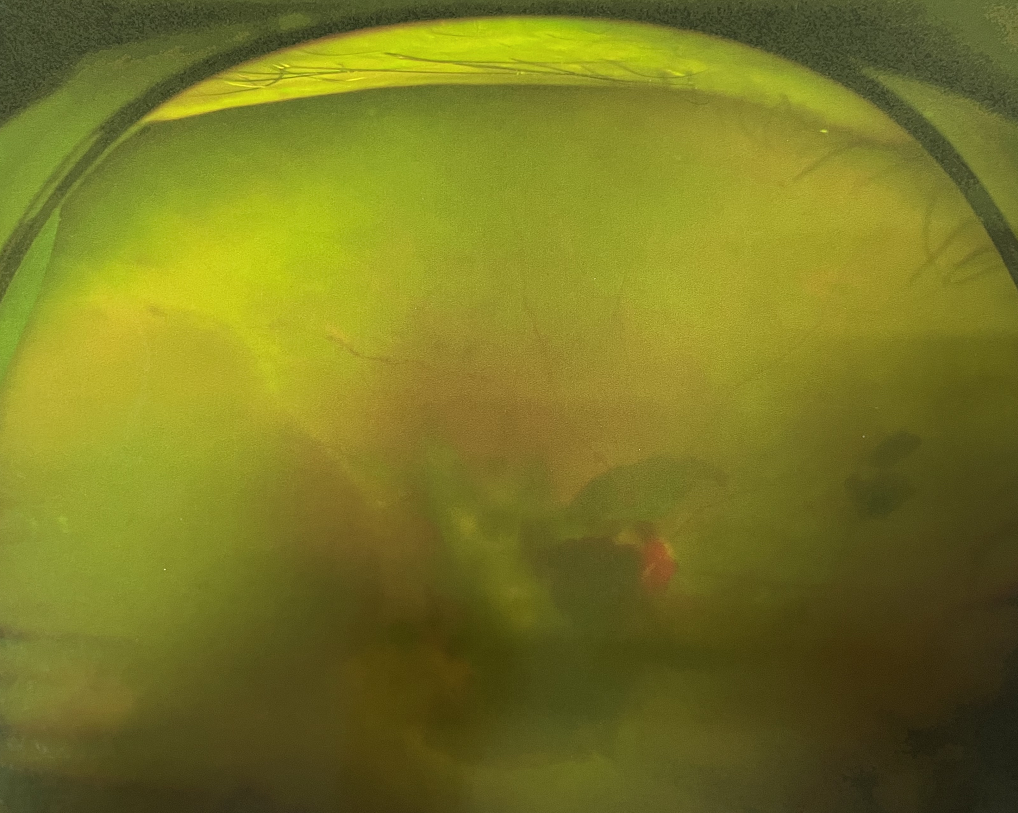

【文章導(dǎo)讀】糖尿病視網(wǎng)膜病變是糖尿病在眼部的主要并發(fā)癥,是我國(guó)四大致盲眼病之一,主要以視網(wǎng)膜血管改變?yōu)椴±硖卣?。眼底多表現(xiàn)為視網(wǎng)膜出血、滲出、新生血管及增殖膜形成,嚴(yán)重威脅患者

糖尿病視網(wǎng)膜病變是糖尿病在眼部的主要并發(fā)癥,是我國(guó)四大致盲眼病之一,主要以視網(wǎng)膜血管改變?yōu)椴±硖卣鳌Q鄣锥啾憩F(xiàn)為視網(wǎng)膜出血、滲出、新生血管及增殖膜形成,嚴(yán)重威脅患者的視覺(jué)健康。

糖尿病視網(wǎng)膜病變

?、羝冢貉鄣子行律芑虿⒂胁Aw積血。

?、跗冢貉鄣子行律芑虿⒂欣w維膜增生。

?、銎冢貉鄣子行律芑虿⒂欣w維膜增生,并發(fā)視網(wǎng)膜脫離。